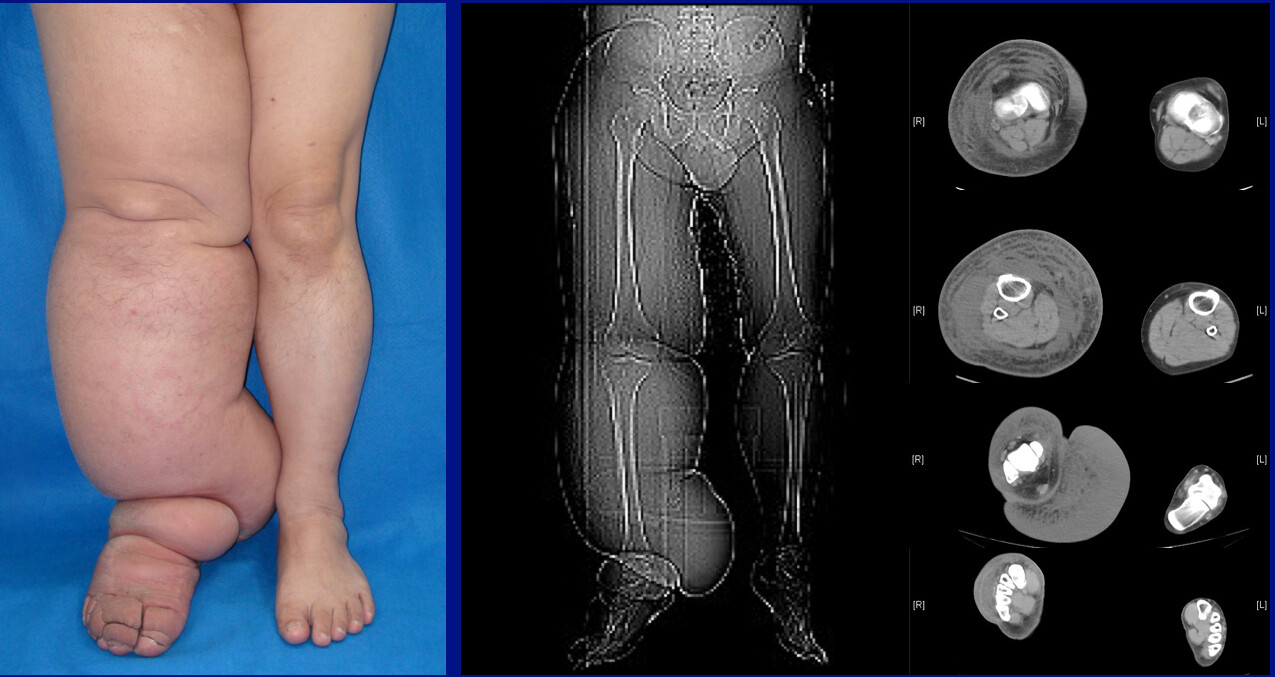

Elephantiasis - removal of lymph nodes, filaria parasites, Miliroy disease